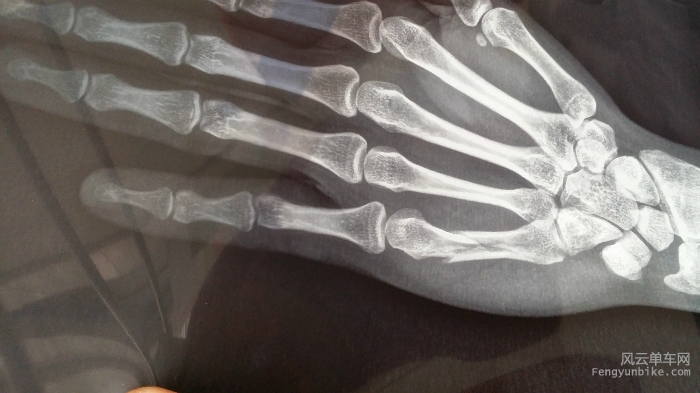

合影完毕后大家一番商讨,直奔燕子口,在燕子口岔道那,我悲催的完成了这次活动的首摔,当时是前几个到达的,想回头看眼大部队的位置,结果忘了解锁。。。。。就悲催的倒在了地上,手变后拨掉漆,袖套破损,左手感觉轻微挫伤,自己活动了下,感觉有骨移位,心里暗自猜想不能使骨折吧,但是强迫自己抛弃了这个想法,时候证明要相信自己的第一直觉,遗憾的是AS100V没电了,没有拍下当时的画面。

回到家后,左手依然肿着,于是匆匆洗了澡开车去了医院,得到的结论是骨折,必须手术

microMsg.1431163453715.jpg

到了北医三,做了固定,在器材室我惊呆了。。。。各种工具,要截肢的感觉,上固定的小大夫人很好,跟我说可以不用手术,做传统治疗,我当时开心了不少